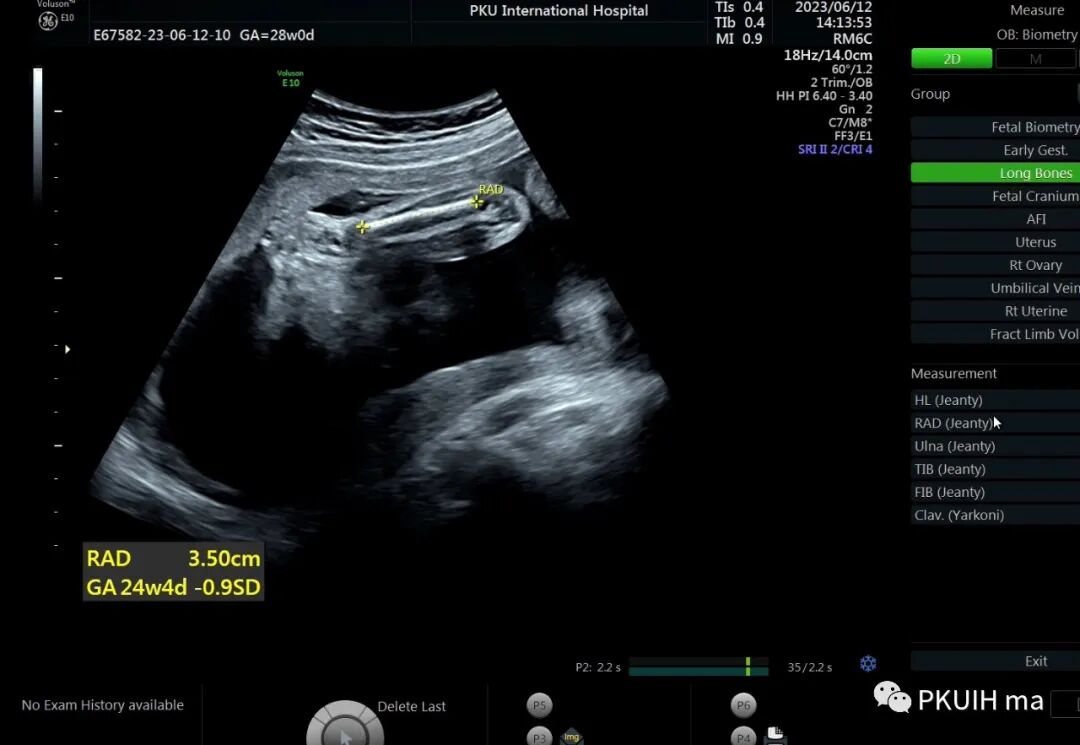

24周+复查发现还是肢体短,生长变慢

28周检查发现肢体越来越短

36周检查发现肢体越来越短,股骨和肱骨只相当于25-6周

大多数孕期发现的骨骼发育不良通常表现为严重的短肢畸形,但足底长度通常不受累。正常时股骨长/足底长度约1:1,<0.87,考虑骨骼发育不良,同时在FGR的诊断中也有帮助。产前超声诊断的主要目的是识别出致死性的骨骼系统发育异常,对临床起到指导意义。区分致死和非致死性骨骼发育异常的主要超声指标有:1、严重的四肢短肢畸形,四肢所有长骨均低于该孕周平均值4个标准差,或股骨长度/胸围<0.16。2、严重的胸廓狭窄:胸围<胎龄的第5百分位,心胸比>0.6(一定要先除外心脏畸形),胸围/腹围比<0.89。3、某些特殊征象,比如严重的颅骨“三叶草样”畸形。